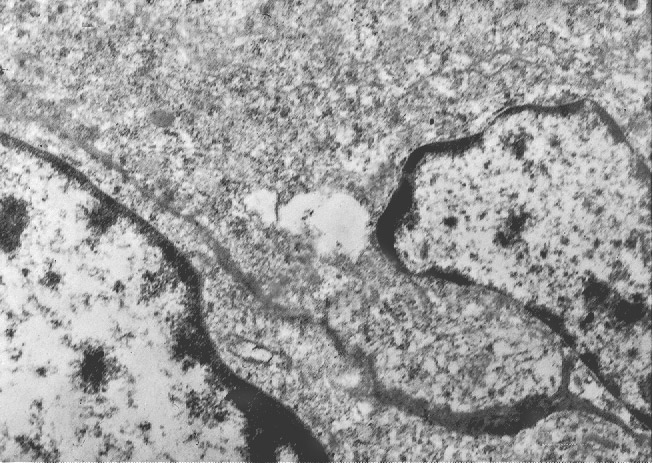

Fig.4

RETICOLO ENDOPLASMICO

Anche il reticolo endoplasmico mostra segni ultrastrutturali di stress sia in associazione all’ergastoplasma sia in situazioni univoche.

Infatti,si repertano cellule di gliosarcoma con l’ ampio citoplasma occupato quasi interamente da queste formazioni; esse sono molto numerose, si trovano tra loro adese e mostrano le loro cisterne ectasiche o micro cistiche, creando così in una visione panoramica una immagine di aspetto cribroso .Lo spazio interno alle cisterne è apparentemente privo di contenuto, o, più raramente, è occupato da materiale amorfo, debolmente elettropaco.